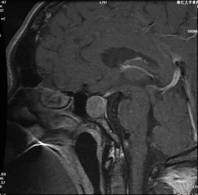

垂体瘤的诊断主要依据相应的临床症状、体征、垂体激素的检测以及影像学的检查。垂体激素在多数医院都能够检测,但要注意垂体激素的分泌节律对取血时间的特殊要求。影像学检查是诊断垂体瘤非常重要的手段,其中以鞍区的核磁共振(MRI)检查对垂体瘤的检出率最高,若结合动态造影MRI检查,多数垂体微腺瘤也可以显像。

神经内镜下经鼻经蝶垂体瘤切除术是近年来新发展起来的一项先进技术。该手术方式克服了显微镜手术的固有缺陷,能提供手术区域清晰的全景图像,解剖结构暴露清楚,可全方位清晰显示肿瘤与周围的重要结构,因此可最大限度地切除肿瘤并降低对正常神经血管的损伤可能。